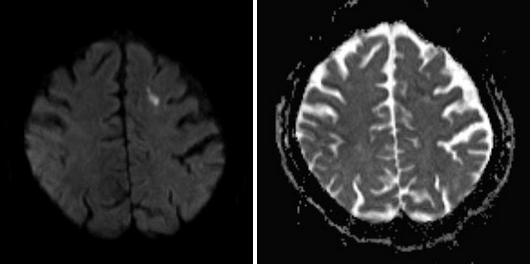

Рисунки 1,2. Диффузионно-взвешенное изображение.

МРТ головного мозга. Определяется очаг ОНМК по ишемическому типу в левой лобной доле (яркий сигнал).